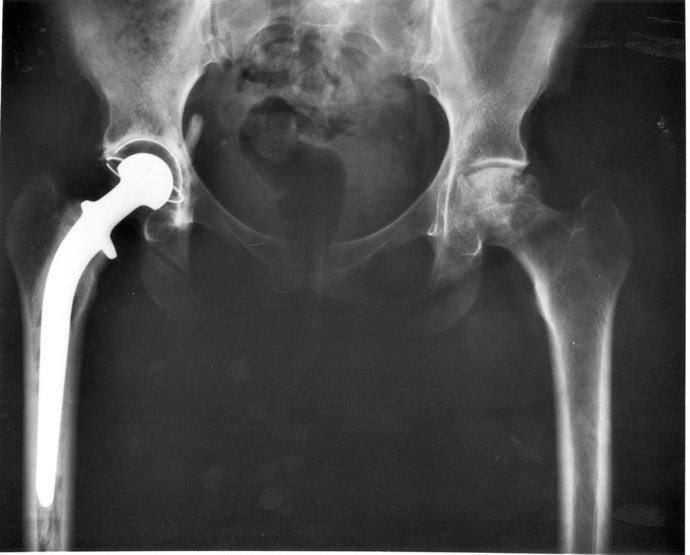

Prótesis De Cadera

WIKIMEDIA/NATIONAL INSTITUTES OF HEALTH EEUU

Asimismo, se calcula que el 12 por ciento de los pacientes con artrosis de rodilla y el 20 por ciento de los pacientes con artrosis de cadera llevan una prótesis.